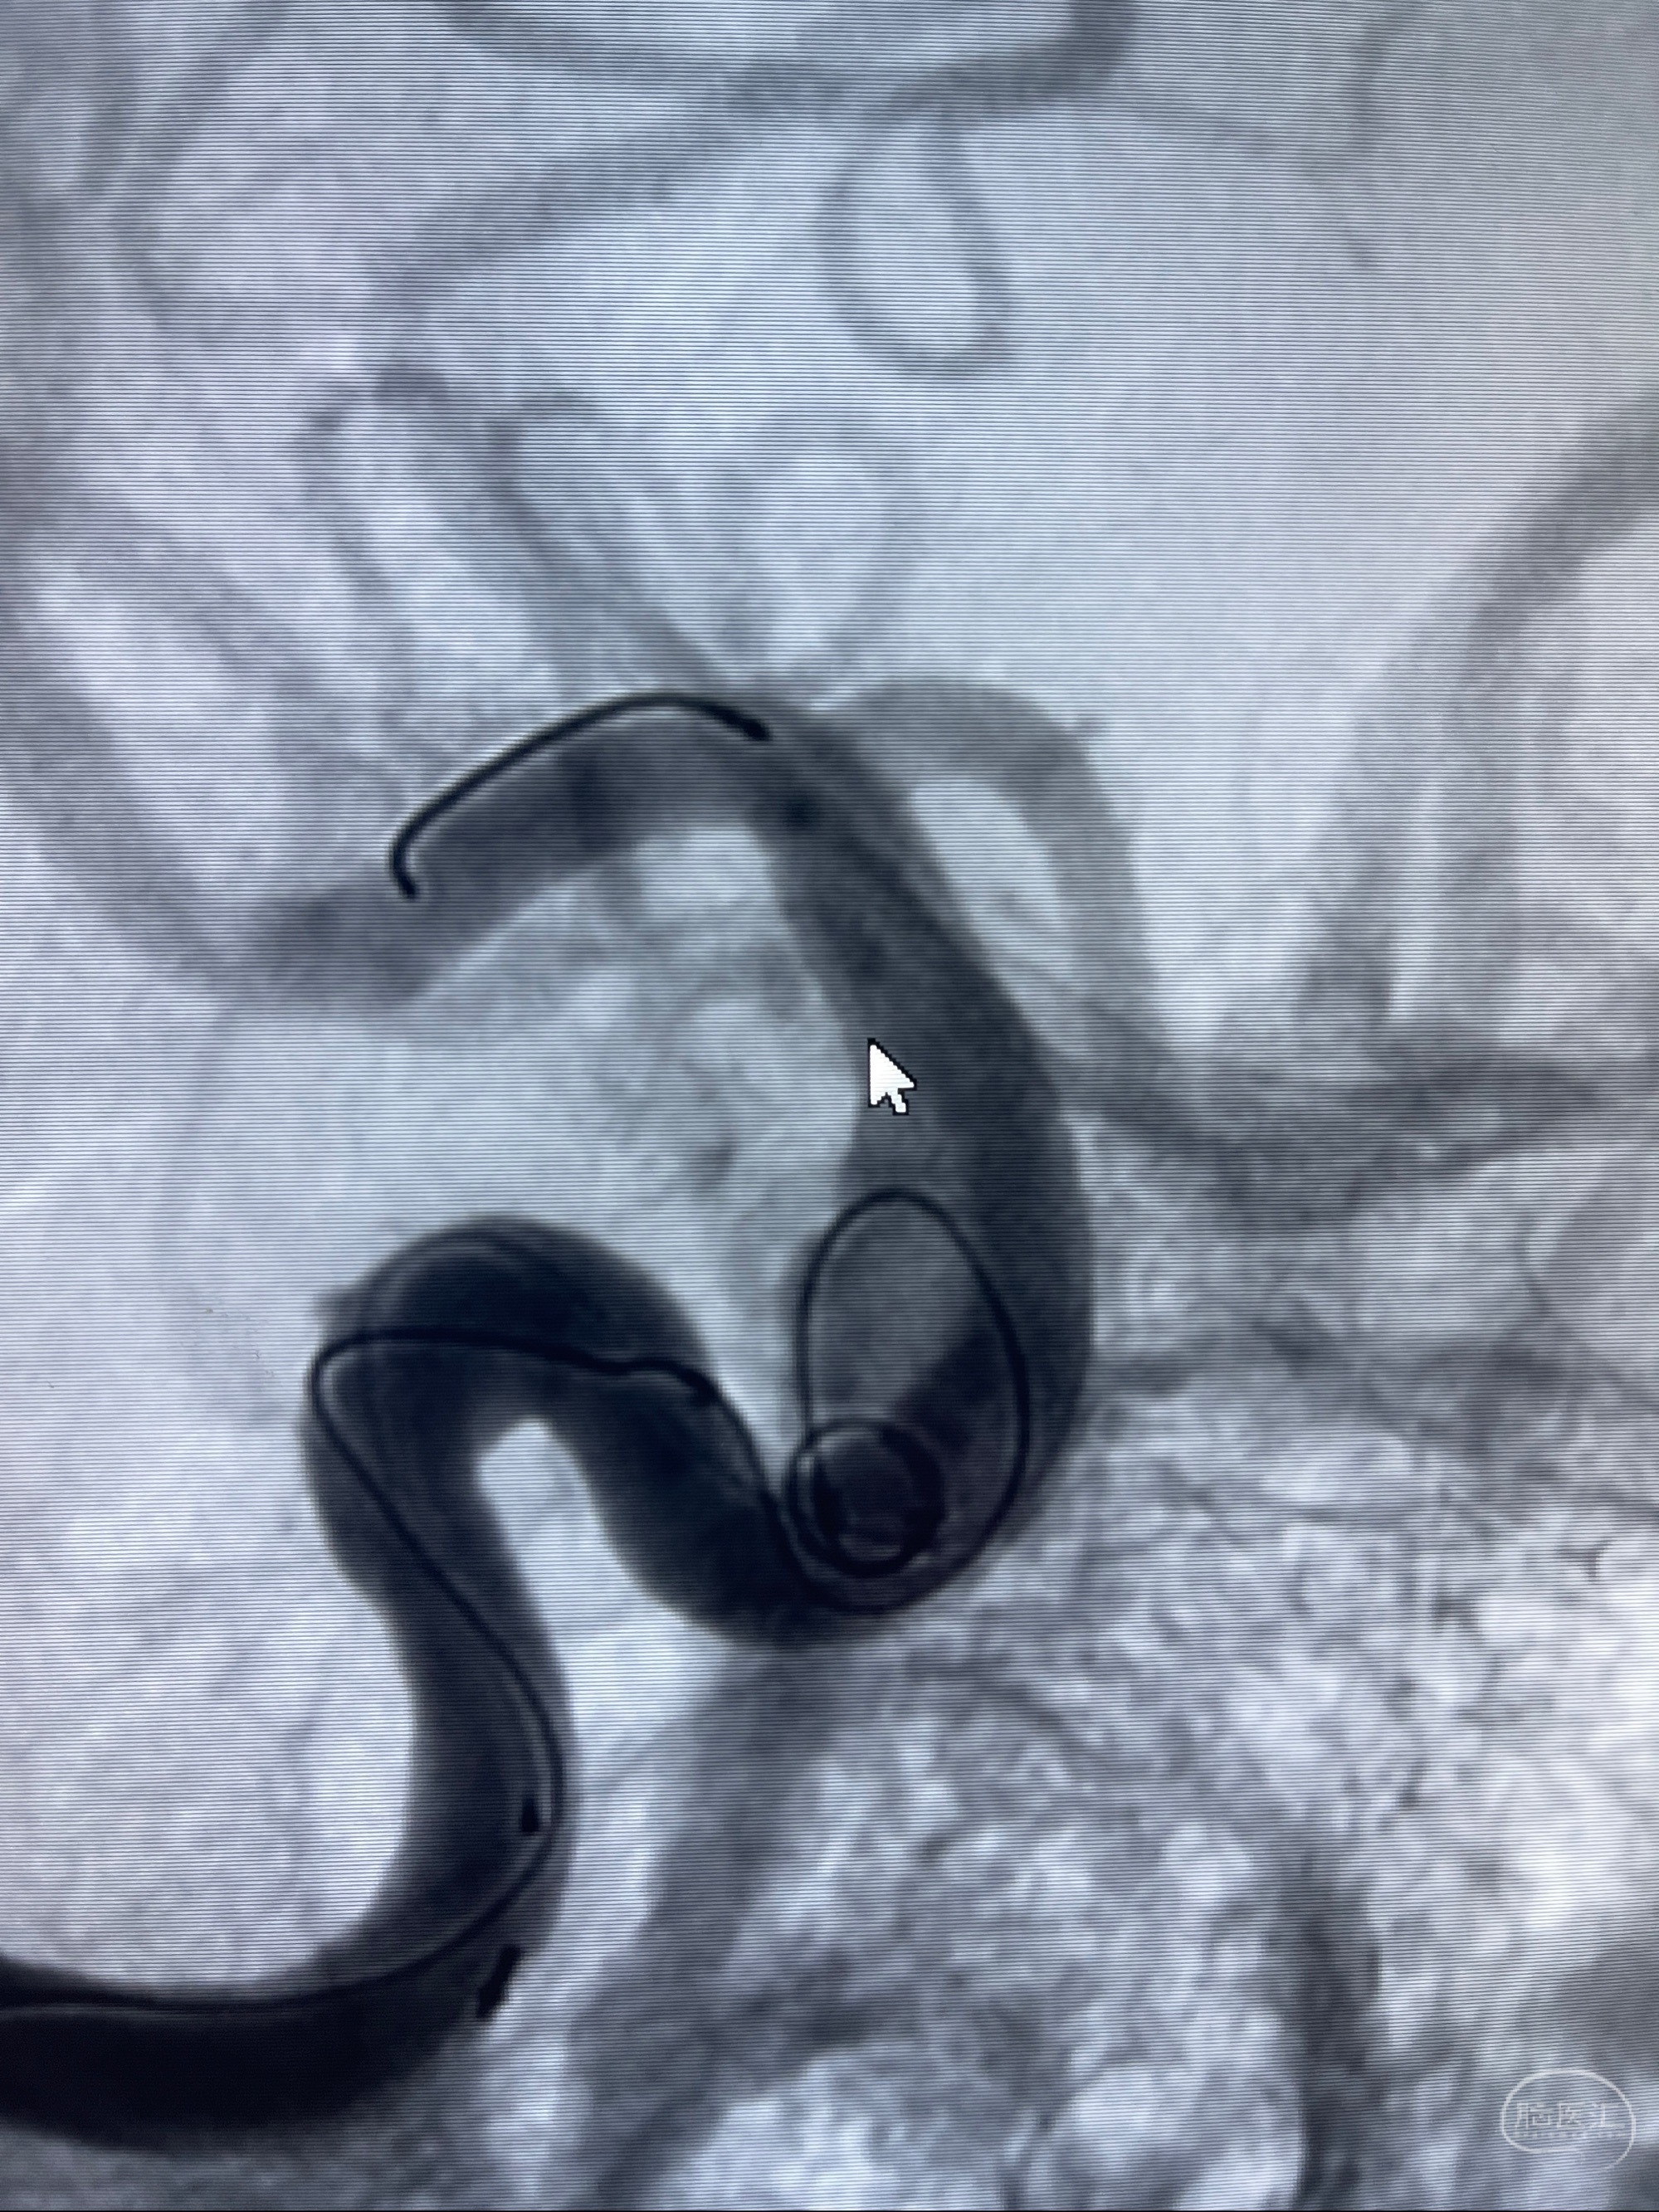

2023-07-27全脑血管造影:双侧颈内动脉眼动脉段动脉瘤,右侧较大

2023-08-01全麻下行双侧颈眼动脉瘤支架辅助栓塞

- pipeling4.5-20mm

- pipeline 4.0-20mm